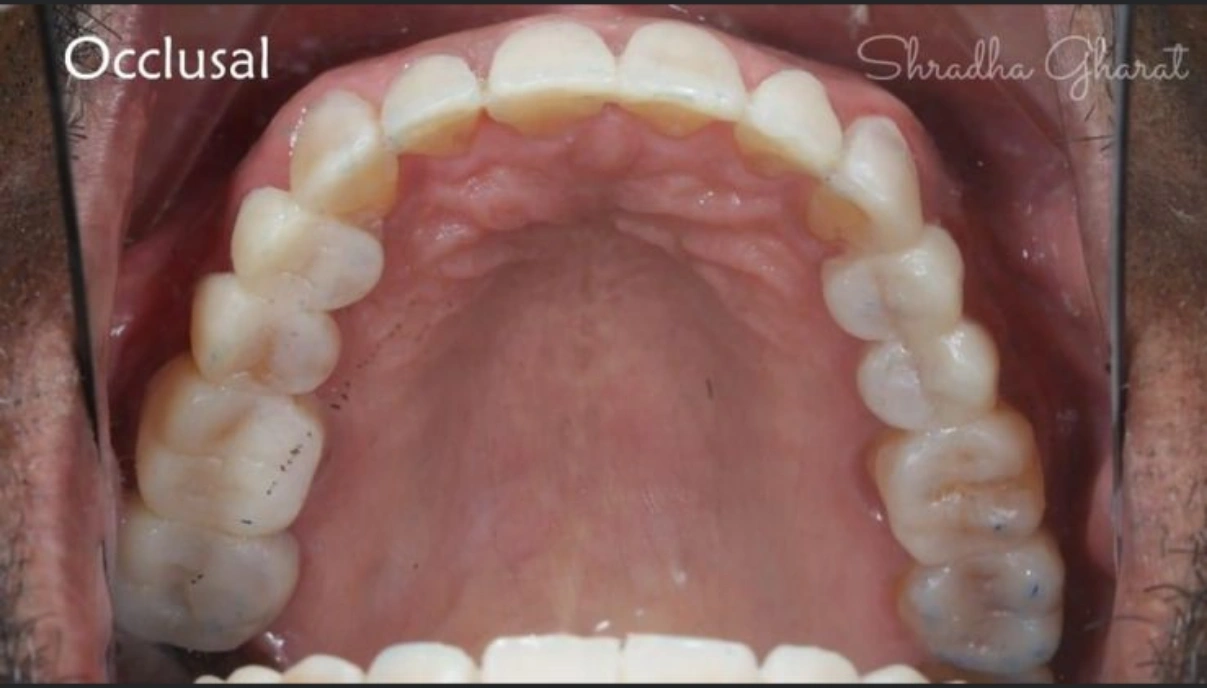

Full mouth rehabilitation includes restoration of lost tooth structure and bite. This technique sensitive procedure involves buildup of lost tooth enamel and dentin. Missing tooth can be replaced with Dental Implants or dental bridges. A Full mouth Reconstruction procedure is mainly indicated for patients with extreme tooth wear.

Full mouth rehabilitation (FMR) is a treatment plan for restoring function and function tolerance of dentition after surgery or dental restoration. It aims to restore dentition to the optimal point of function and esthetics of a healthy mouth. The treatment plan provides patients with a permanent smile that looks natural and bright.